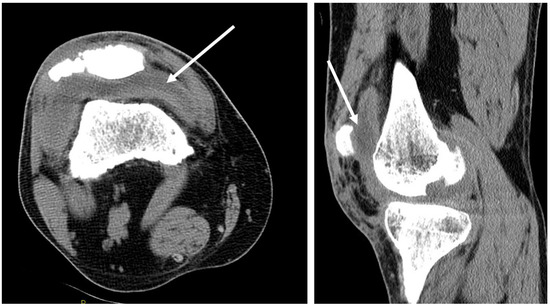

3.4. Osteoarticular Manifestations of Coccidioidomycosis and in This Patient